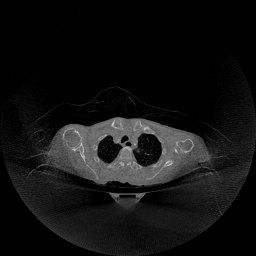

The experimental results on clinical head data are shown in Fig. 4. The reference images were reconstructed using the fast iterative shrinkage-thresholding algorithm (FISTA) with total variation regularization from non-truncated projection data. In the WCE reconstructions (Fig. 4(b)), severe truncation prevents accurate recovery of anatomical structures outside the FOV. Despite being trained solely on simulated data with a domain gap, all deep learning models can restore a substantial portion of the missing anatomy. Among them, the diffusion-based methods recover soft-tissue boundaries more faithfully than the conventional deep learning approach FBPConvNet, highlighting their stronger image generation capability. However, cDDPM reconstructions exhibit more noticeable noise than those from other methods, consistent with the simulated data results. The patchDiffusion model introduces artifacts within the FOV, likely due to its patch-wise processing strategy. While I2SB shares the same limitations as other diffusion models in perfectly restoring soft-tissue detail, it produces fewer residual noise patterns and fewer artifacts within the FOV boundaries. Overall, Fig. 4 demonstrates the strong efficacy of I2SB in reconstructing real CBCT data.